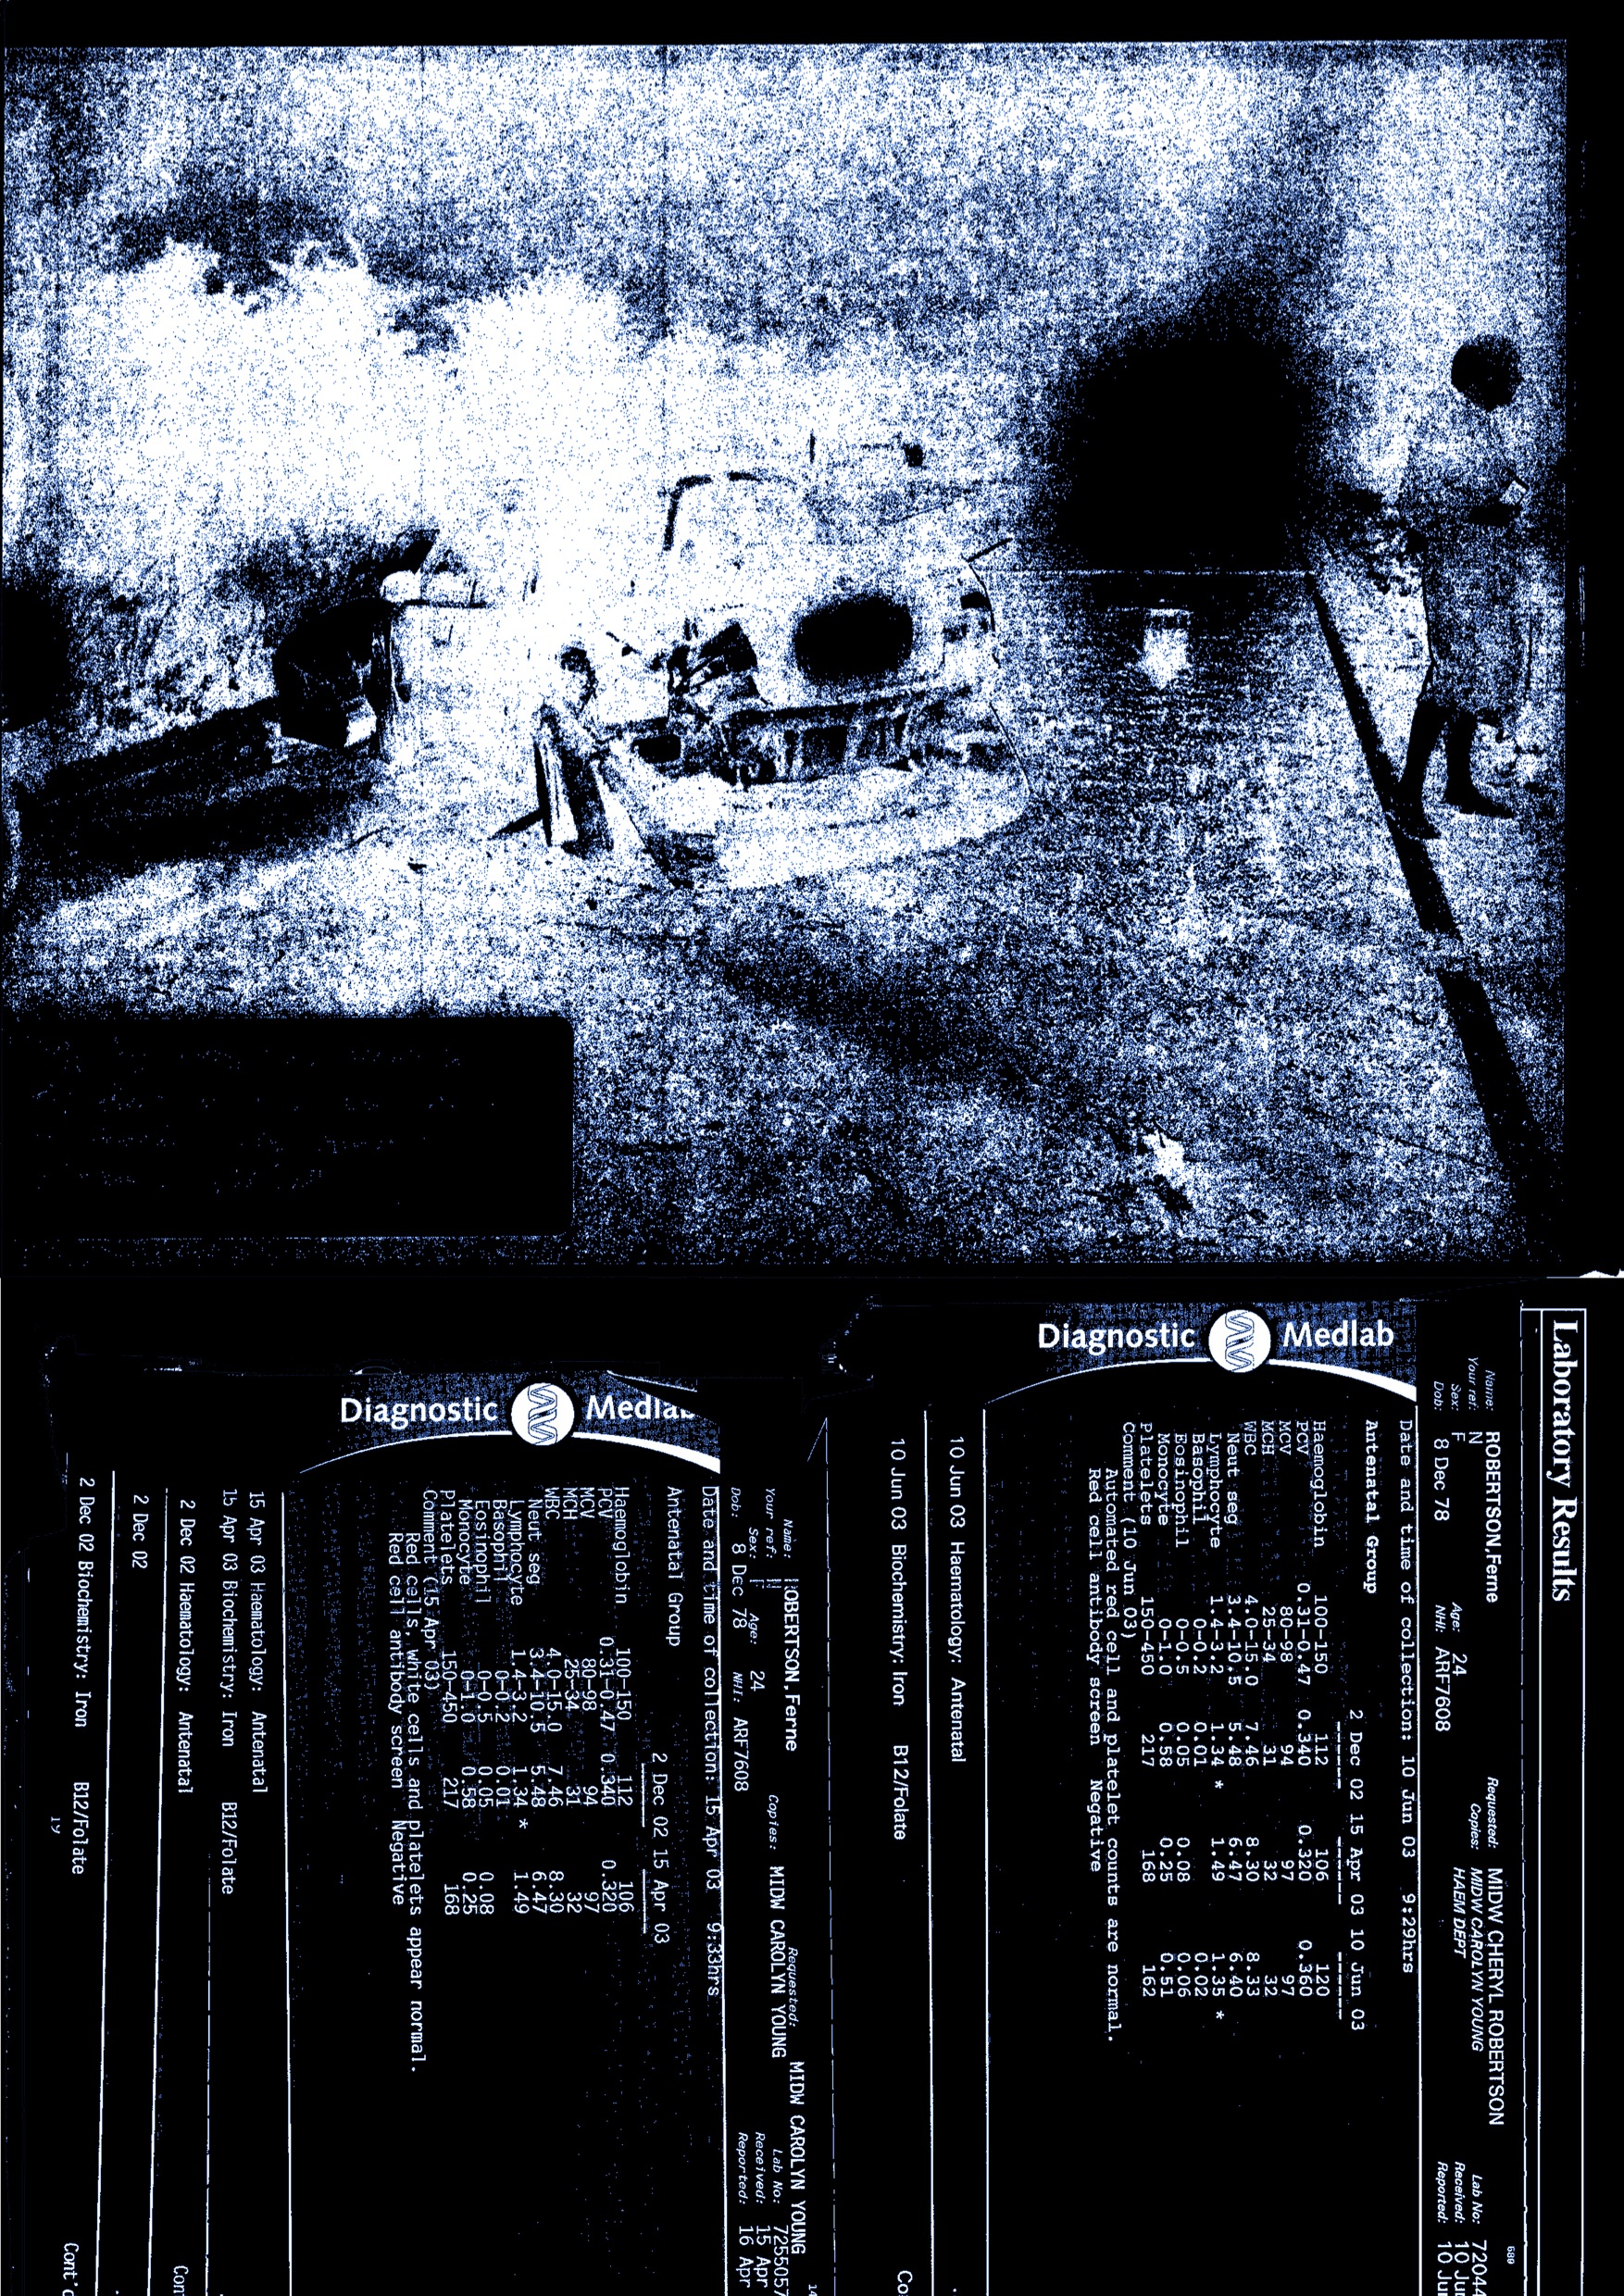

Documentation of Various Indicidents, Found objects, Crutches, Plaster,

Medical Wrap, Moon Boot, House Paint, Car Mats, Wetsuit, Projection, Casts, Video Work Forensics investigates trauma both physical and mental and how the two might interact through objectivity.